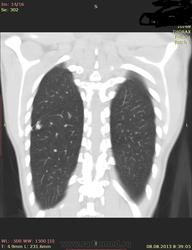

Здраствуйте, коллеги. Нужна ваша помощь молодая девушка 21 г. в течении 2-х лет беспокоит субфибрильная температура, период.гол. боль. В прошлом году сделала ОГК зак: туберкулема. Ей сказали что она перенесла тбс. на ногах, лечение не принимала. Сдавала все анализы без изменении.Родная сестра 3 года назад перенесла тбс.

Туберкулёма в 6-ке.

Распада не вижу, очагов отсева тоже. Контроль и к фтизиатру.

По показанным изображениям данных за активность нет, но без дайкома однозначно не сказать. Посмотрите в MIP при толщине среза 4-6 мм очаги. Если у девушки иммунодефицит любого генеза, то картина даже через несколько дней может кардинально поменяться, так что в любом случае конс.фтизиатра.

Справа в С6 - неправильной округлой формы образование повышенной интенсивности с включениями извести. Данное образование связано с корнем лёгкого бронхо-сосудистой "дорожкой". Рекомендовано анализ мокроты на МБТ!